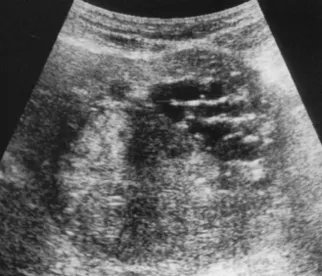

● 肝内无数个无回声区。

● 大者边界清,形态一般欠规整。

● 内透声好。

● 后方结构(后壁)回声增强。

● 无囊肿部位肝组织回声增强增粗。